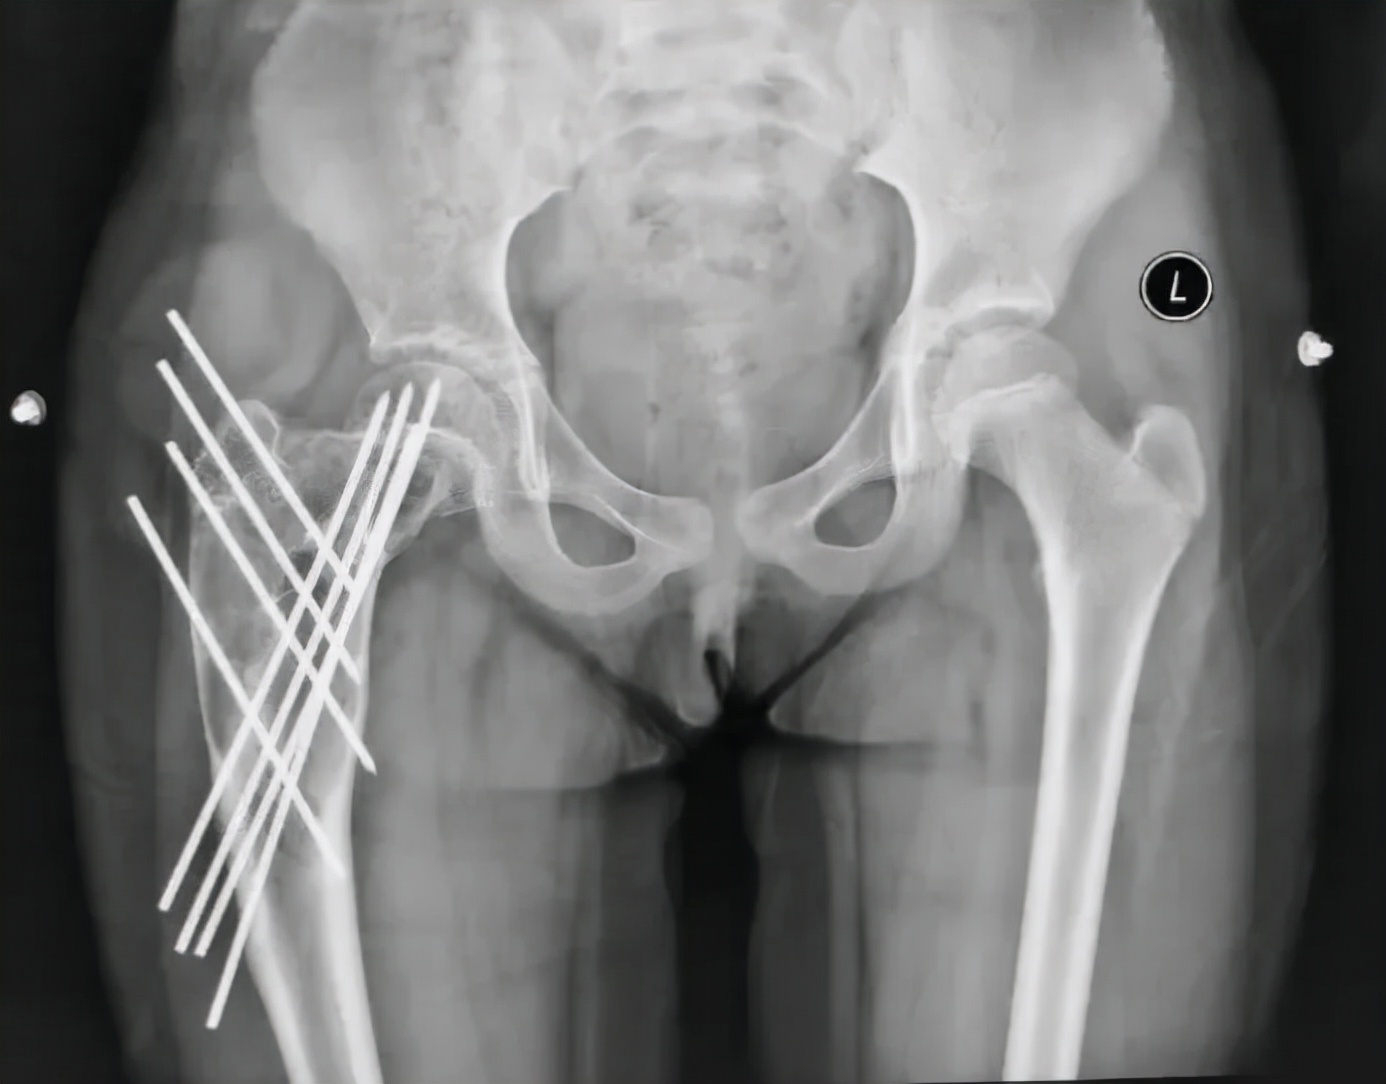

孩子上三年级,酷爱跳舞,获得过青少年舞蹈比赛一等奖,一天练习的时候,突然髋关节疼痛,站立困难,经当地医院拍片检查,提示股骨近端巨大的骨破坏引发的病理性骨折!按照孩子的话说,就是“从此告别了热爱和坚持的舞蹈!”遭此意外,对每个家庭而言,无异于灭顶之灾。

我接诊后,通过临床、影像和病理的综合研判,确诊为股骨近端动脉瘤样骨囊肿,这类疾病虽是良性肿瘤,但病变范围大,复发率高,破坏严重,对生长发育期儿童,可能导致肢体畸形、跛行等严重后果,若治疗选择不当,更会导致雪上加霜。经过慎重考虑,结合以往的病例治疗经验,我采用了微创的治疗方法,手术后6周患儿即开始下地活动,术后3个月就逐步开始舞蹈训练了,孩子的梦想得以继续。

从影像学看,这个孩子手术后股骨近端留置多根钢针,术后2年左右的时间,尽管股骨强度有增加,但是骨囊肿还未愈合,并出现了部分退针的情况,孩子身高已经比第一次手术时长了近10cm了,选择什么样的治疗方案再次摆到面前,当我决定更换固定针,继续使用微创治疗理念时,患儿家长对于可能出现的针道激惹等并发症表示了完全的理解,并认真了解了术后相关的注意事项,正是因为家长的配合,手术之后患儿就能够进入快速康复。